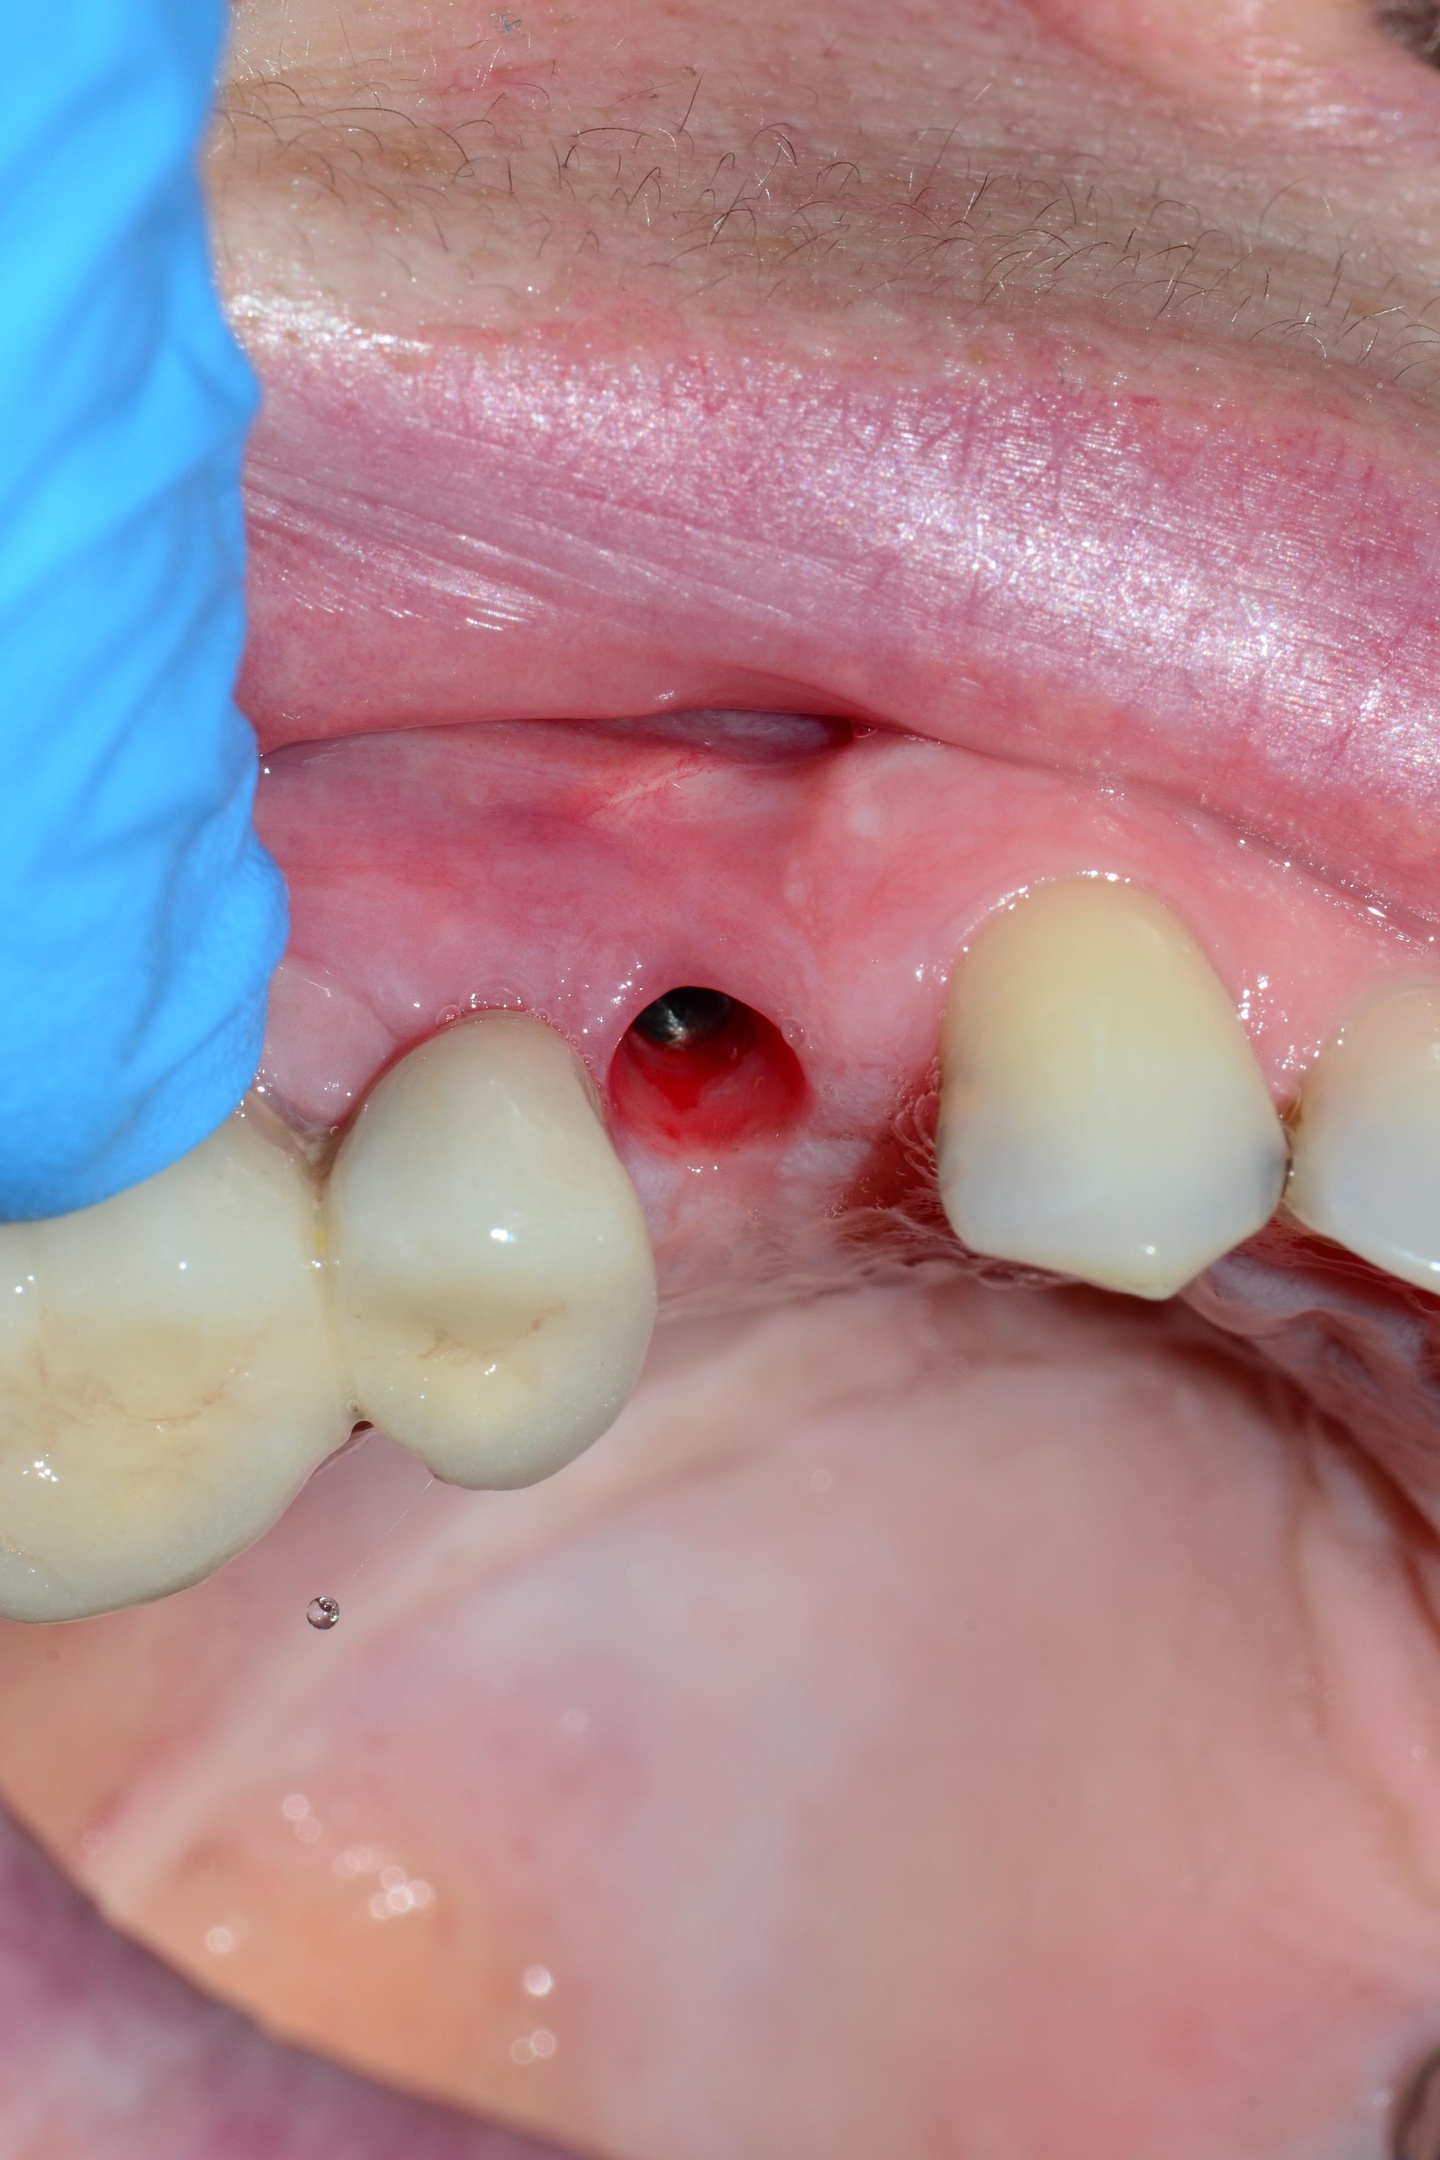

Stabilnost mekog tkiva – često zanemaren faktor

Meko tkivo oko implanta ima zaštitnu ulogu:

sprečava prodor bakterija

smanjuje rizik od periimplantitisa

olakšava održavanje oralne higijene

Upravo zbog toga, položaj implanta u odnosu na desni, izbor protetskog rešenja i hirurška tehnika često imaju veći uticaj na dugoročni uspeh nego sam izbor sistema.